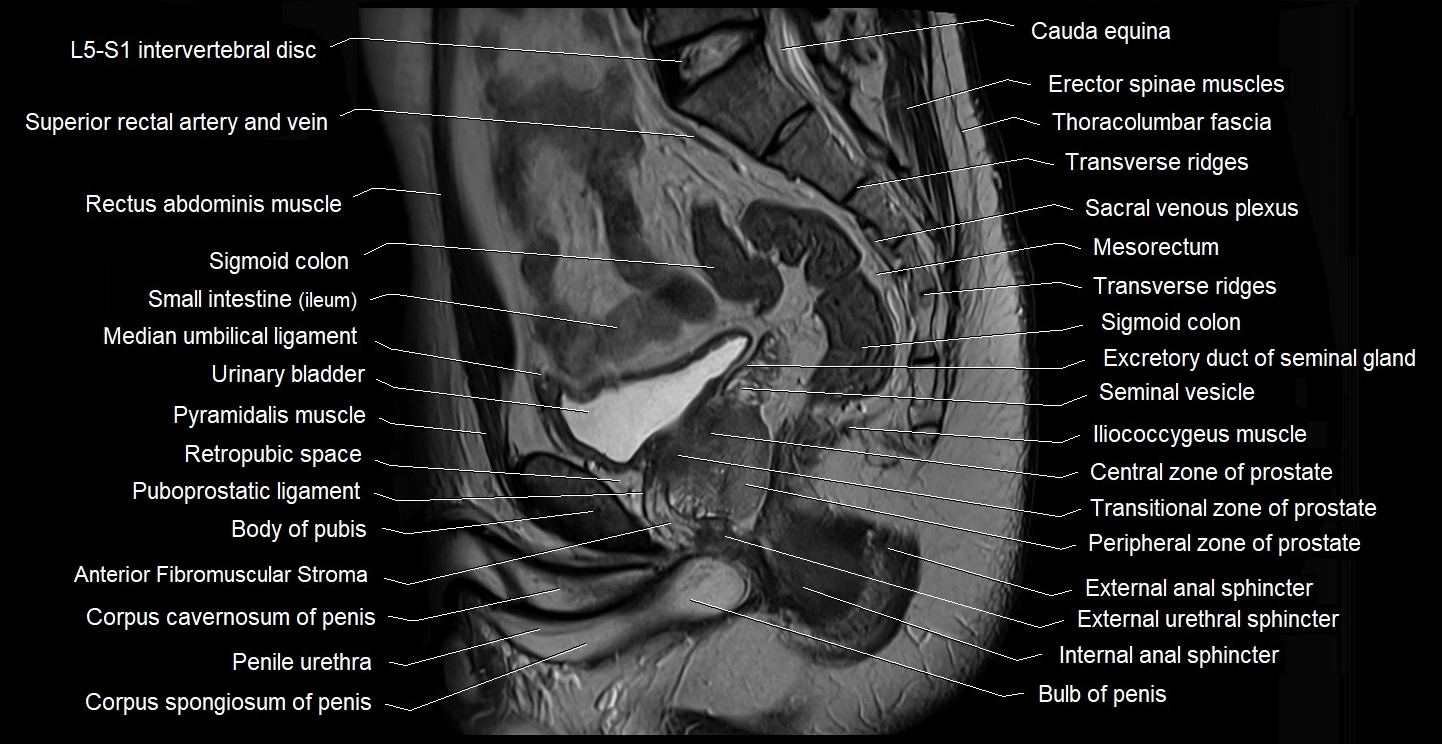

- Anterior Fibromuscular Stroma of prostate

- Body of pubis

- Bulb of Penis

- Central zone of prostate

- Corpus cavernosum

- Corpus spongiosum

- External anal sphincter

- External urethral sphincter (male)

- Iliococcygeus muscle

- Internal anal sphincter

- Median umbilical ligament

- Mesorectum

- Penile urethra

- Peripheral zone of prostate

- Puboprostatic ligament

- Pyramidal muscle (pyramidalis muscle)

- Retropubic space

- Seminal vesicle

- Transitional zone of prostate

- Transverse ridges